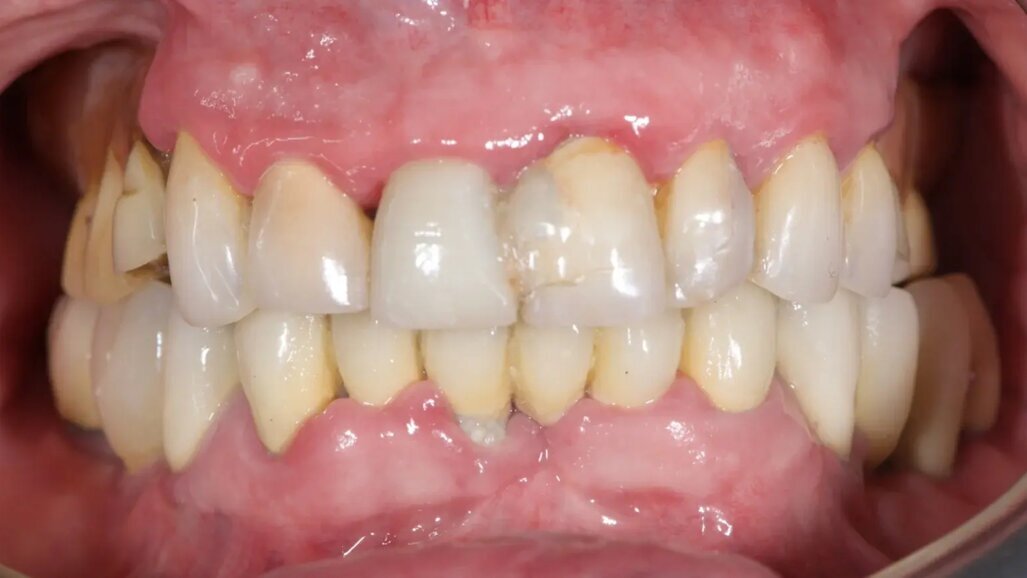

Фиг. 2: Начална ситуация, оклузален изглед.

85-годишен пациент с частично обеззъбяване беше насочен към нашата клиника за рехабилитация на цялата горночелюстна дъга. Пациентът беше в добро общо здравословно състояние, непушач. Основните му оплаквания включваха затруднения при дъвчене, болка в горната челюст и периодична халитоза. Клиничната и рентгенографската оценка разкриха фиксирана металокерамична протеза с къс обхват, задържана върху седем предни зъба на горната челюст. Протезата се беше отлепила и четири от опорните зъби бяха структурно увредени. Останалите три показваха различна степен на кариес и пародонтални проблеми. Беше поставена диагноза за компрометирано съзъбие.